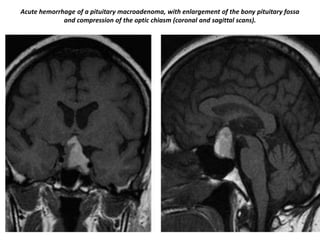

Acute hemorrhage of a pituitary macroadenoma, with enlargement of the bony pituitary fossa

and compression of the optic chiasm (coronal and sagittal scans).